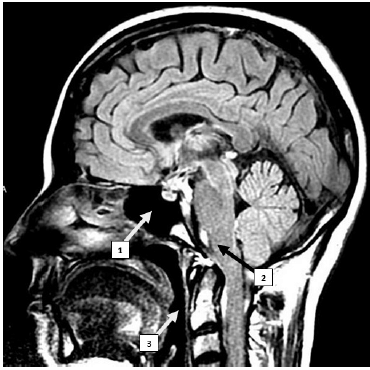

A estrutura indicada pelo número 1 corresponde ao seio etmoidal, uma cavidade oca revestida com mucosa e preenchida com ar.